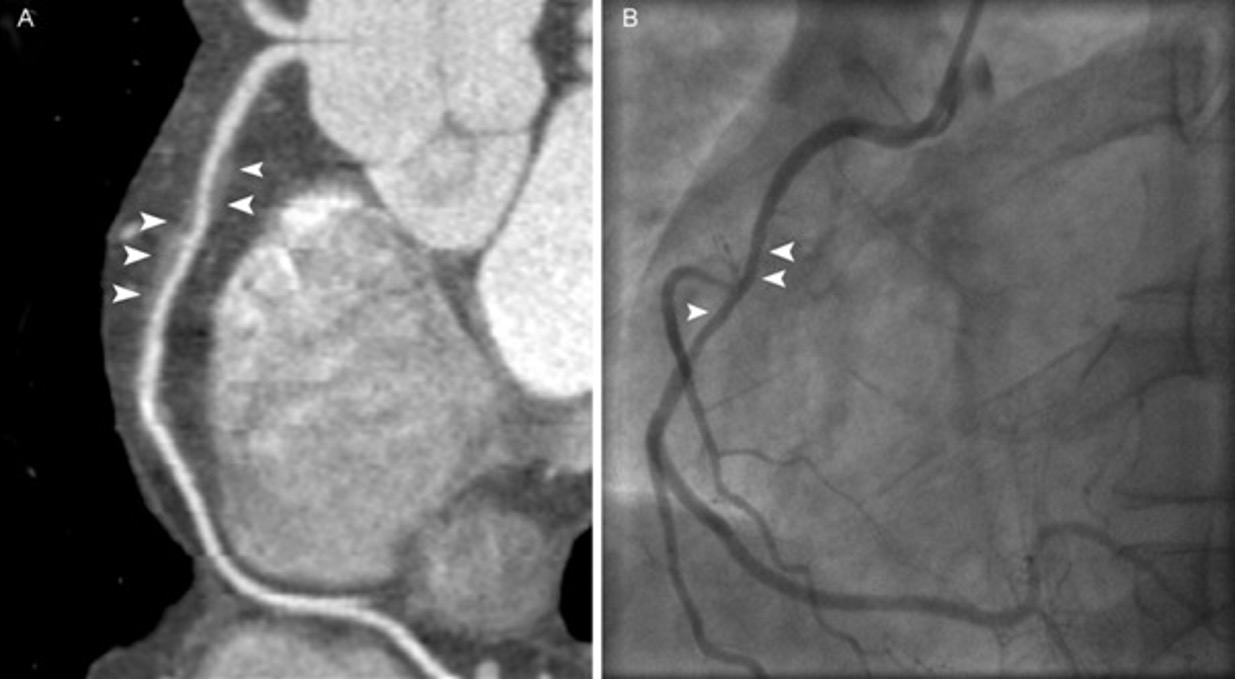

A computerised tomography (CT) coronary angiogram is an imaging test that looks at the arteries that supply blood to your heart. It might be used to diagnose the cause of chest pain or other symptoms.

A CT coronary angiogram relies on a powerful X-ray machine to produce images of your heart and its blood vessels. These tests are non-invasive and don’t require recovery time. Coronary CT angiograms are increasingly becoming an option for people with a variety of heart conditions.

A coronary CT angiogram can check your heart for various conditions, but it’s primarily used to check for narrowed or blocked arteries in your heart (coronary artery disease). If your test suggests that you have heart disease, you and your health care provider can discuss treatment options.

FFR-CT, or Fractional Flow Reserve derived from Coronary CT Angiography, is a non-invasive technique that uses CT scans to simulate the blood flow through coronary arteries, to assess the severity of blockages and guide treatment decisions. This provides your doctor with a 3D model of your coronary arteries (arteries that supply blood to your heart) as a way to identify any narrowing in the coronary arteries.

(FFRCT) is a physiologic simulation technique that uses routine CTA data to mathematically model coronary flow, pressure, and resistance

The most commonly used and approved technique, Heart Flow uses computational fluid dynamics (CFD) with off-site supercomputers. A patient-specific three-dimensional (3D) anatomic coronary artery model is obtained by using semiautomatic contouring and segmentation. A physiologic model is then derived based on patient-specific inflow and outflow hemodynamic conditions, with the resting myocardial blood flow proportional to the myocardial mass, and the microvascular resistance inversely proportional to the size of epicardial coronary arteries.

The addition of FFRCT to coronary CTA improves its specificity by evaluating lesion-specific ischemia, enhances its role as a gatekeeper for ICA by decreasing nonobstructive disease at ICA, and offers guidance for revascularization decisions and planning. The accuracy of FFRCT and superior specificity compared with that of coronary CTA has been well established on both off-site and on-site platforms in multiple studies.

An FFRCT value greater than 0.8 is normal, values between 0.76 and 0.8 are borderline, and a value less than or equal to 0.75 is abnormal.